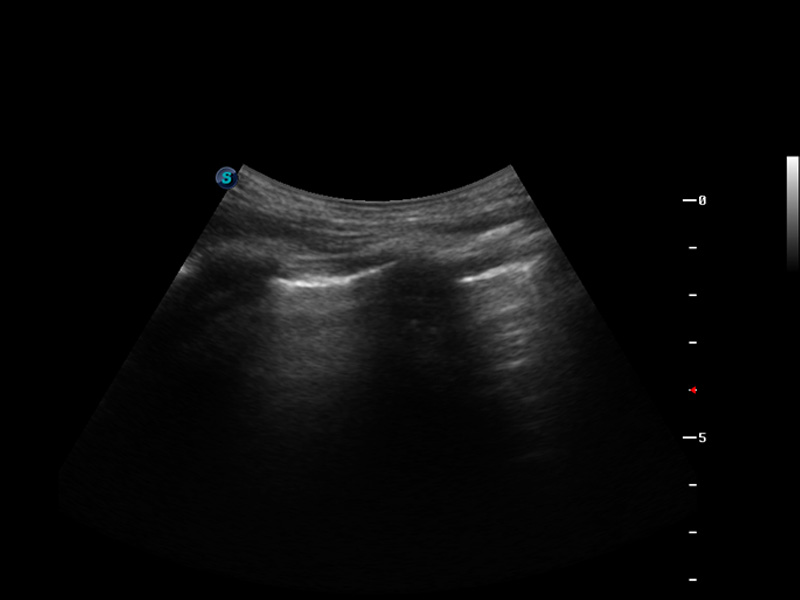

S9

S9便携式彩色多普勒超声诊断仪是1xBET研发的高端便携彩超设备,外观设计新颖、产品性能卓越。S9在便携超声领域采用了突破传统的触摸屏交互设计,并以先进的软件硬件技术和设计理念,为您带来清晰的图像质量、稳定的工作性能和便捷的操作体验。